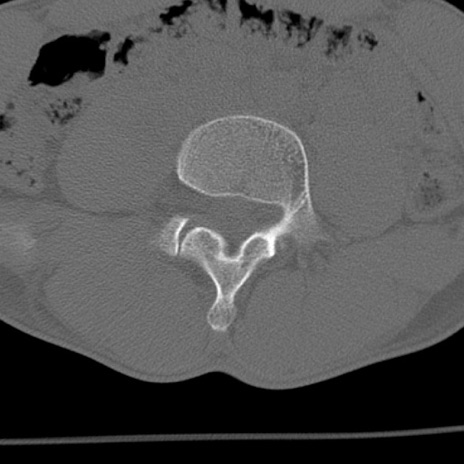

症例3 腰椎CT(横断像)

腰椎CT